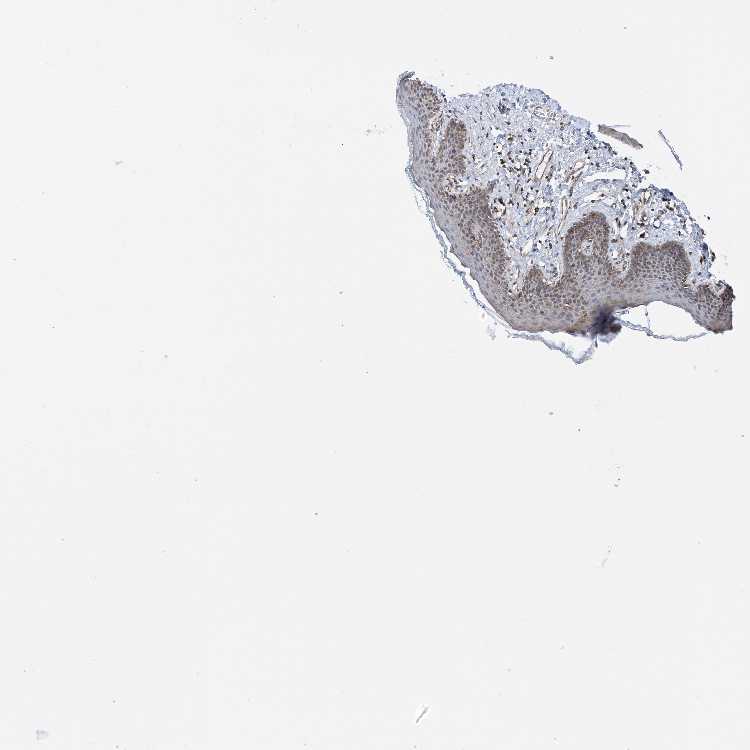

SKIN 1 - Antibody stainingi

Antibody staining in the annotated cell types in the current human tissue is reported as not detected, low, medium, or high, based on conventional immunohistochemistry profiling in selected tissues. This score is based on the combination of the staining intensity and fraction of stained cells.

Each image is clickable and will lead to virtual microscopy that enables deeper exploration of all samples and also displays staining intensity scores, fraction scores and subcellular localization as well as patient and tissue information for each sample.

Antibody HPA035013

Langerhans Medium

Fibroblasts Medium

Keratinocytes Medium

Melanocytes Medium

SKIN 2 - Antibody stainingi

Epidermal cells Medium